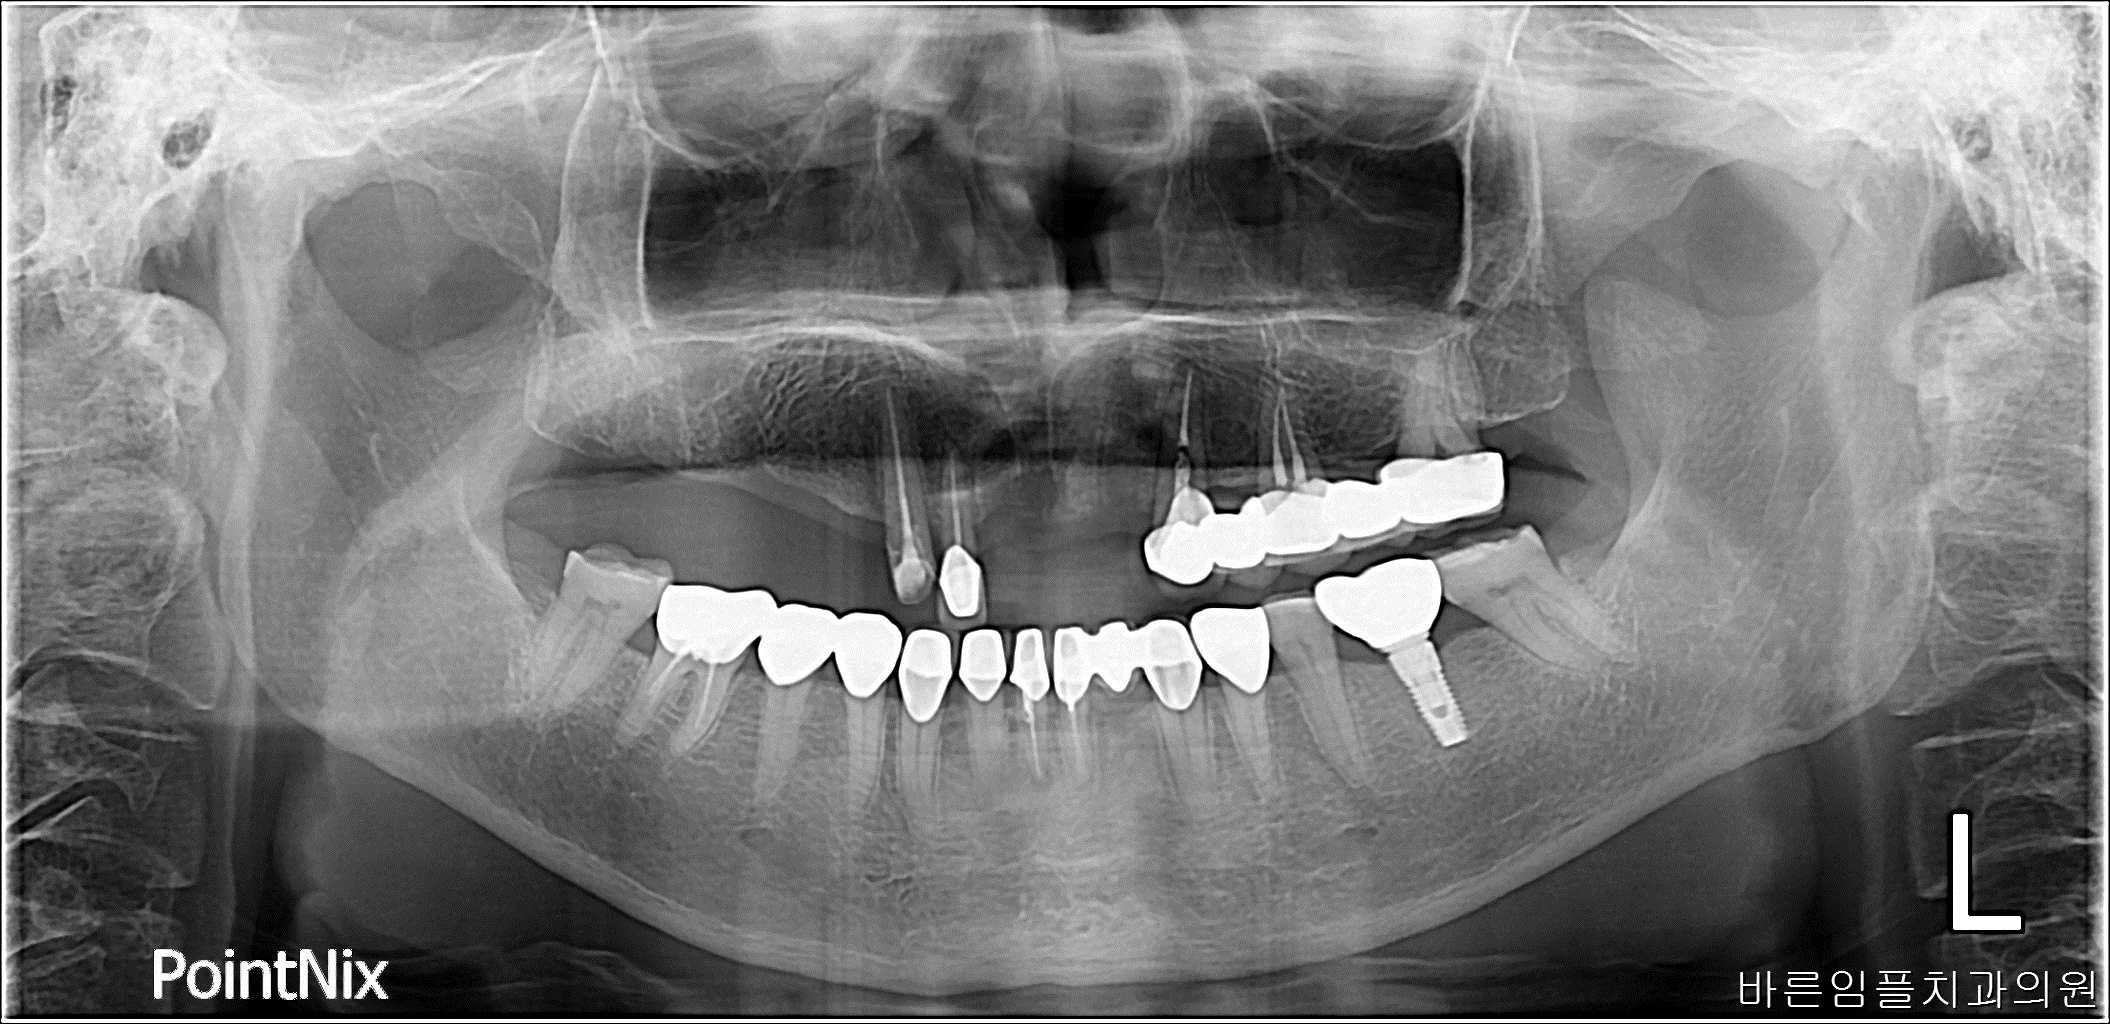

차ㅇㅇ / 수면임플란트 페이지 정보 작성일 23-10-27 17:06 2021-03-10 차ㅇㅇ Before 2023-03-16 차ㅇㅇ After 차ㅇㅇ / 수면임플란트 목록 다음글 이ㅇㅇ / 수면임플란트